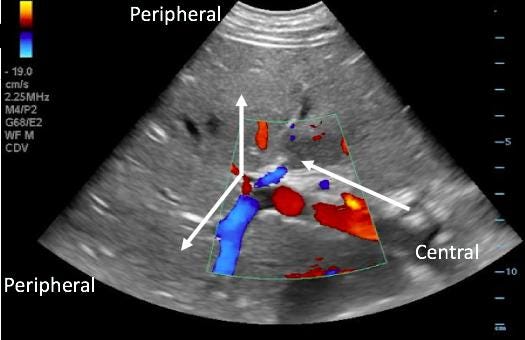

Step 3: Portal Vein Doppler

How to Obtain the View

Use coronal approach similar to hepatic vein

Slide caudally to visualize liver and kidney

Fan anteriorly to identify portal vein

Place Doppler gate in main portal vein (avoid hepatic artery overlap)

Interpretation

PVPF <30% → normal

30–50% → mild

50% → severe

Pitfalls

Cirrhosis altering baseline

Respiratory variation mimicking pulsatility

Hepatic artery contamination

Incorrect gate placement